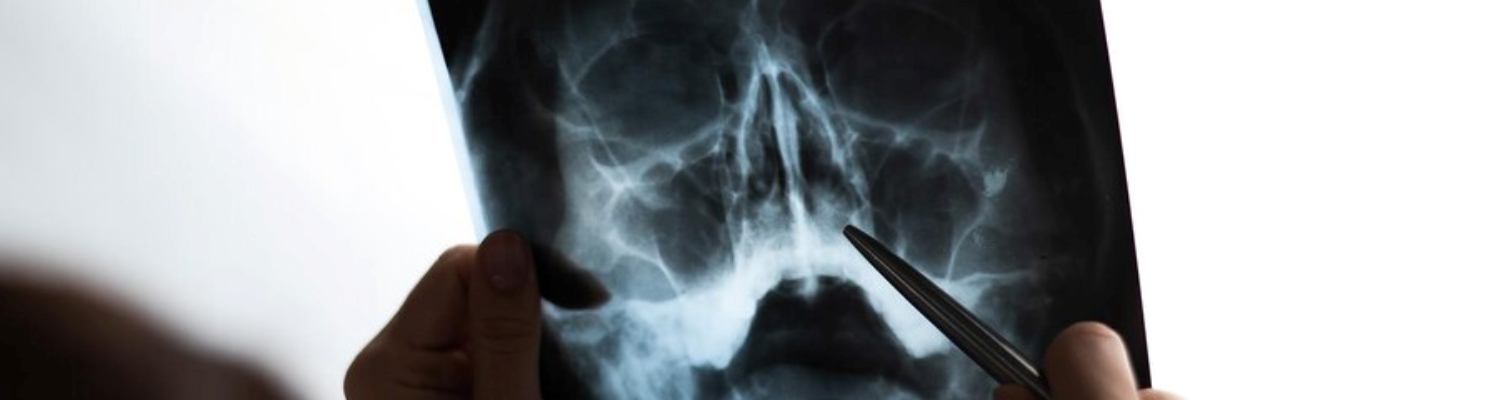

Рентгенография придаточных пазух носа в МЦ "Healthy&Happy" в Киеве

Рентгенография придаточных пазух носа — это один из наиболее информативных методов диагностики, который позволяет выявить воспалительные процессы, аномалии развития и новообразования в носовых пазухах. Исследование помогает своевременно поставить диагноз и разработать эффективный план лечения.

В медицинском центре Healthy&Happy в Киеве рентген придаточных пазух проводится на современном оборудовании, обеспечивающем безопасность для пациентов и высокую точность результатов. Благодаря минимальной дозе облучения эта процедура абсолютно безопасна для большинства пациентов.

- Процесс: Врач-радиолог делает снимки в нескольких проекциях (прямая и боковая), что позволяет оценить состояние гайморовых, лобных и решетчатых пазух.